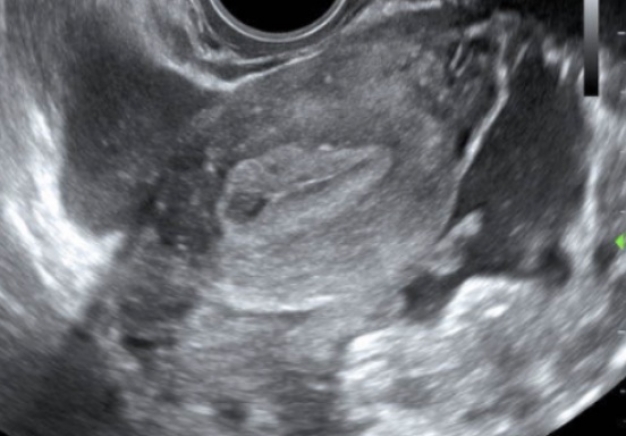

Bedside point of care ultrasound is performed and reveals the following images (shown below). What’s the diagnosis? Scroll down for answer.

Trans vaginal US - Mid uterus

Answer: Ruptured Cornual (ie Interstitial) Ectopic Pregnancy

For example, our patient had what LOOKED to be a gestational sac in the uterus, but it was actually a pseudogestational sac (see mid uterus view above). Upon further investigation, we found the complex adnexal mass in addition to the intrauterine ‘sac’.